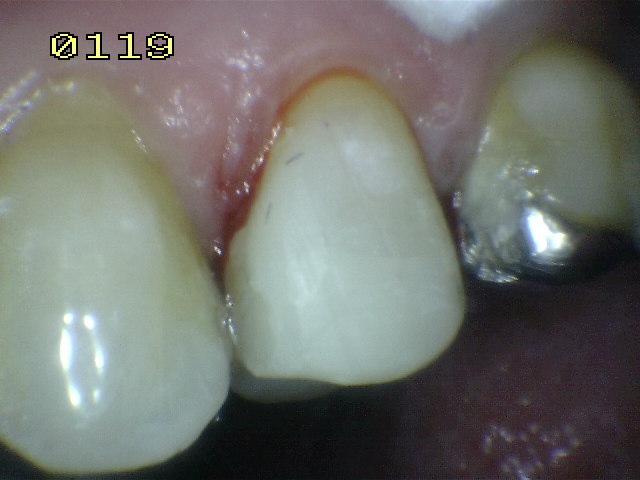

| También se

baja la cúspide vestibular o de corte , para prevenir

una fractura dental.. |

| Se cubre

el esmalte y dentina co una fina capa de resina flow y

se polimeriza durante 20 segundos. |

Se

compacta la resina compuesta hibrida en

capas no mayor de 2 mm. |

Hasta darle la

morfología oclual adecuada. |

Reconstrucción

terminada. |